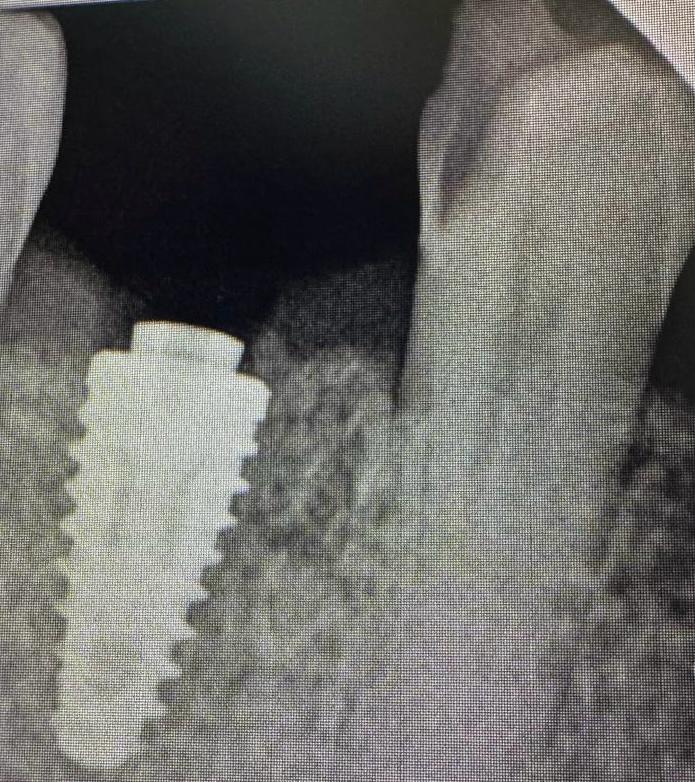

Dr Matshidiso Mphahlele-Ntladi is an accomplished dental professional whose extensive qualifications and experience underscore her commitment to excellence in oral health care. With a robust educational background, she holds a Diploma in Oral Hygiene, a Bachelor’s Degree in Dental Therapy, a Bachelor’s Degree in Dentistry, and a Postgraduate Diploma in Aesthetic Dentistry. Additionally, she possesses a Dispensing License and is currently pursuing a Postgraduate Diploma in Implantology, demonstrating her dedication to continuous learning and staying at the forefront of dental innovations.

Furthermore, her ongoing pursuit of advanced education in implantology reflects her ambition and commitment to professional growth. Dr. Mphahlele-Ntladi is not only a skilled clinician but also a lifelong learner, always seeking to expand her knowledge and enhance her practice.